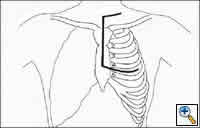

Figure Figure

Figure 4: Incision for a right hemi-clamshell (Bains MS et al. The clamshell incision: an improved approach to bilateral pulmonary and mediastinal tumor. Ann Thorac Surg 1994;58:30-33. Used with permission) Figure 5: Operative exposure for a right hemi-clamshell (Bains MS et al. The clamshell incision: an improved approach to bilateral pulmonary and mediastinal tumor. Ann Thorac Surg 1994;58:30-33. Used with permission)